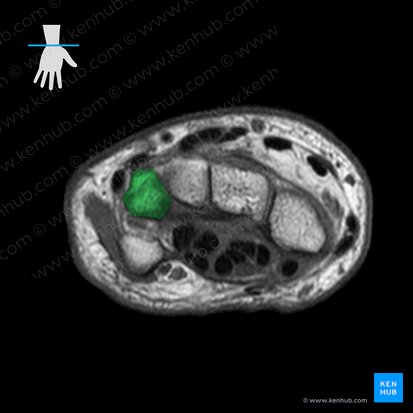

We’ll follow a similar approach to the previous axial MRI to describe the visible structures. We’ll start with the skeletal framework i.e. the hyperintense bones. Quite a lot has changed at this level. Only the radial styloid process is visible on the extreme right hand side of the image and three carpal bones have become visible. Moving from right to left, you can see the scaphoid, lunate and triquetrum. If you know the anatomy of the proximal row of carpal bones, the order and location are quite obvious. The shape of the bones can guide you as well. The scaphoid resembles a boat, the lunate has a crescent (moon) shape and the triquetrum resembles a pyramid.

Ligaments

In contrast to the previous MRI image, there are several ligaments apparent in this axial view. You can see two thick, grey structures (intermediate intensity) spanning the superior and inferior margins of the radius, scaphoid and lunate bones. These are two extrinsic ligaments of the radiocarpal joint that connect the radius to each carpal bone; the dorsal and palmar radiocarpal ligaments. As their names imply, the dorsal radiocarpal ligament is located superiorly on the dorsal aspect. Its palmar counterpart is found inferiorly on the palmar aspect. Between the scaphoid and lunate bones you can see a thick, grey, interconnecting band. This is an intrinsic ligament of the radiocarpal joint which interconnects adjacent carpal bones. It is called the scapholunate interosseous ligament.